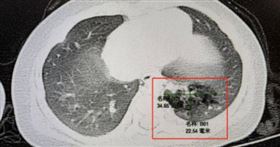

45歲女走路喘「以為3高」 竟是心臟破洞

台中豐原一名45歲林姓女子,近期走路時覺得喘,以為只...